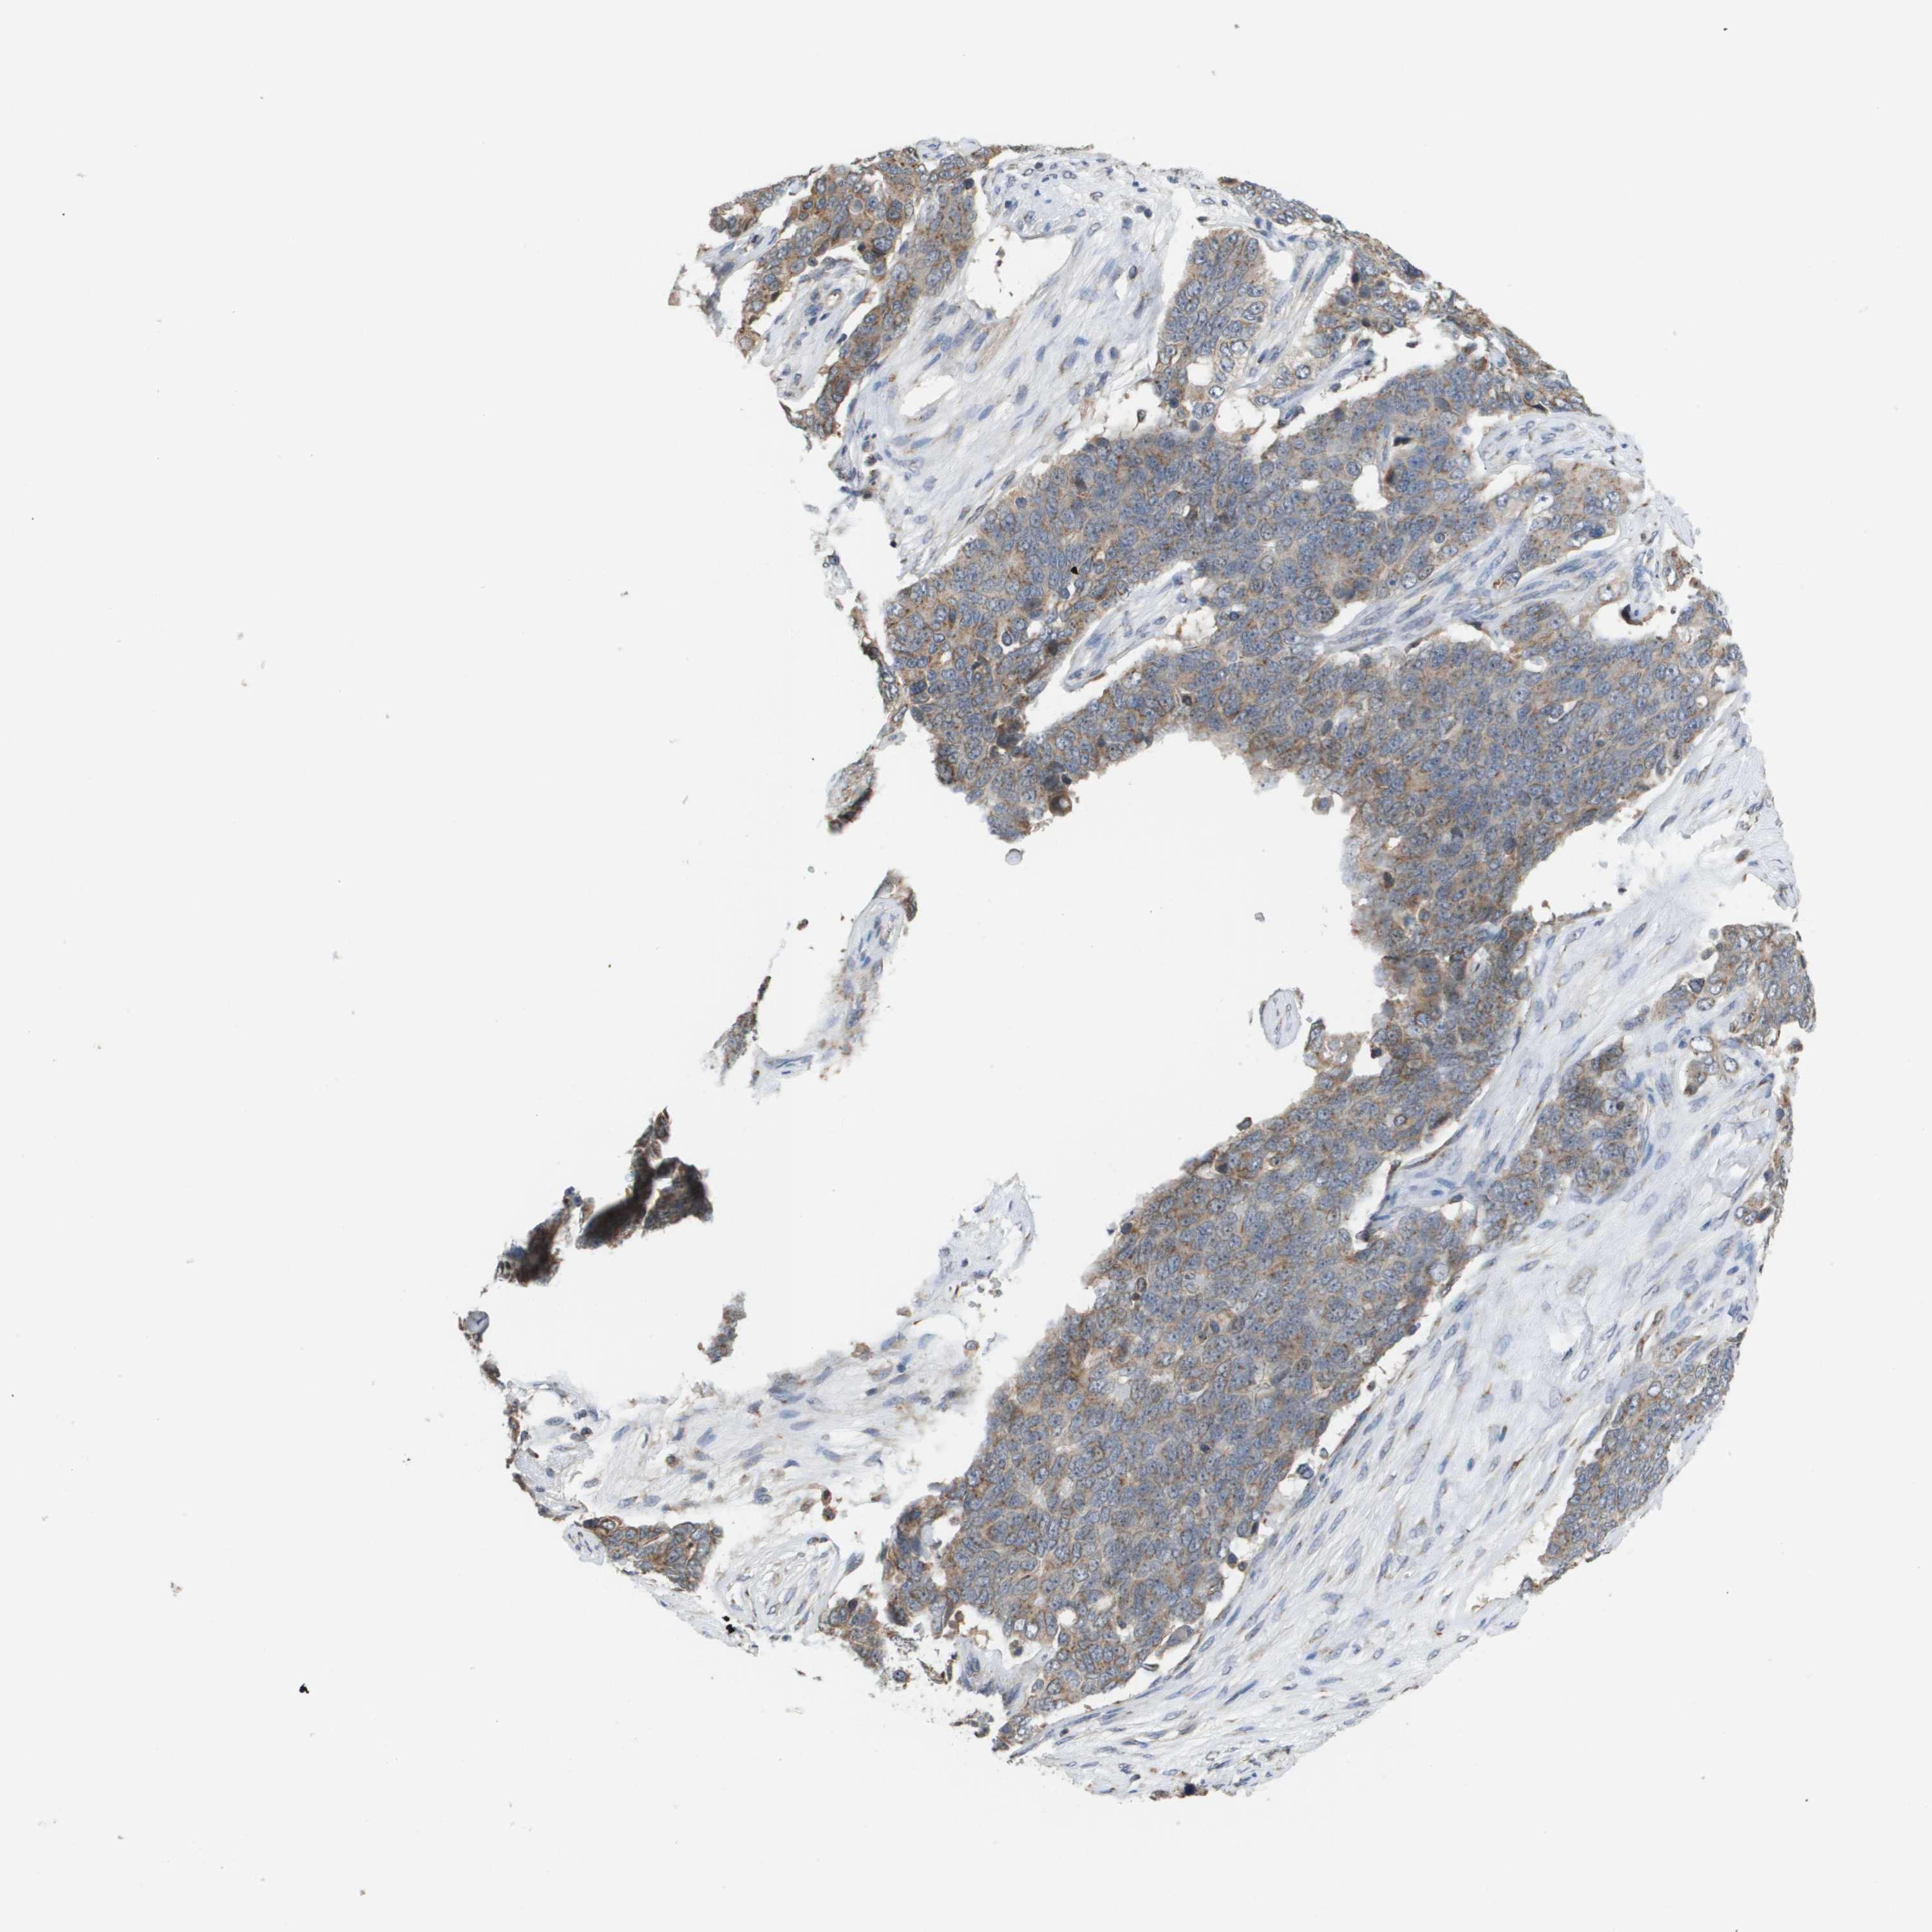

OVARIAN CANCER - Protein expressioni

A mouse-over function shows sample information and annotation data. Click on an image to view it in a full screen mode. Samples can be filtered based on level of antibody staining by selecting one or several of the following categories: high, medium, low and not detected. The assay and annotation is described here.

Note that samples used for immunohistochemistry by the Human Protein Atlas do not correspond to samples in the TCGA dataset.

Antibody stainingi

Antibody staining in the annotated cell types in the current human tissue is reported as not detected, low, medium, or high, based on conventional immunohistochemistry profiling in selected tissues. This score is based on the combination of the staining intensity and fraction of stained cells.

Each image is clickable and will lead to virtual microscopy that enables deeper exploration of all samples and also displays staining intensity scores, fraction scores and subcellular localization as well as patient and tissue information for each sample.

Antibody HPA006277

Staining

High

Medium

Low

Not detected

Cystadenocarcinoma, serous, NOS